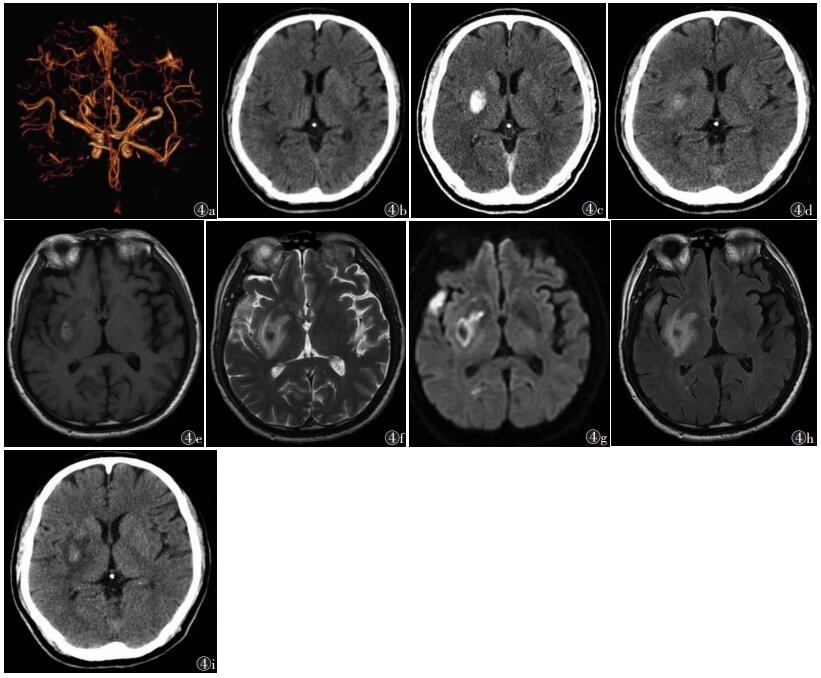

Ⅲ型高密度影CT值41~116 HU, 48 h后复查,复查过程中高密度影周围均有不同程度水肿并引起占位效应;14例(40.00%)高密度影进行性增大,21例(60.00%)范围缩小,密度减低(图 4)。

| 注:患者,男,64岁,突发言语含糊不清伴左侧肢体活动不能4 h余。图 4a为术前头颈动脉及椎动脉CTA,示右侧大脑中动脉水平段局部闭塞;图 4b为术前颅脑CT,未见明显异常;图 4c为术后即刻CT,示右侧基底节片状高密度影,CT值约83 HU,周围无明显水肿,局部脑组织略肿胀,邻近脑沟变窄;图 4d为术后第2天复查CT,示高密度影密度减低,体积缩小,周围见片状低密度区,轻度占位效应;图 4e~4h分别为术后第4天MRI轴位T1WI、T2WI、DWI、FLAIR图像,示右侧基底节病灶呈T1WI高、低信号,T2WI、DWI及FLAIR呈低、高混杂信号,周围见片状T1WI低信号,T2WI、FLAIR高信号,DWI低信号,轻度占位效应,符合右侧基底节梗死并出血、周围水肿的MRI表现,另右侧颞叶见片状T1WI低信号,T2WI、DWI、FLAIR高信号,符合梗死灶MRI表现;图 4i为术后第6天复查CT,示高密度影密度较上次略增高,周围低密度区增大,轻度占位效应 图 4 Ⅲ型急性缺血性脑卒中MRI及CT图像 |